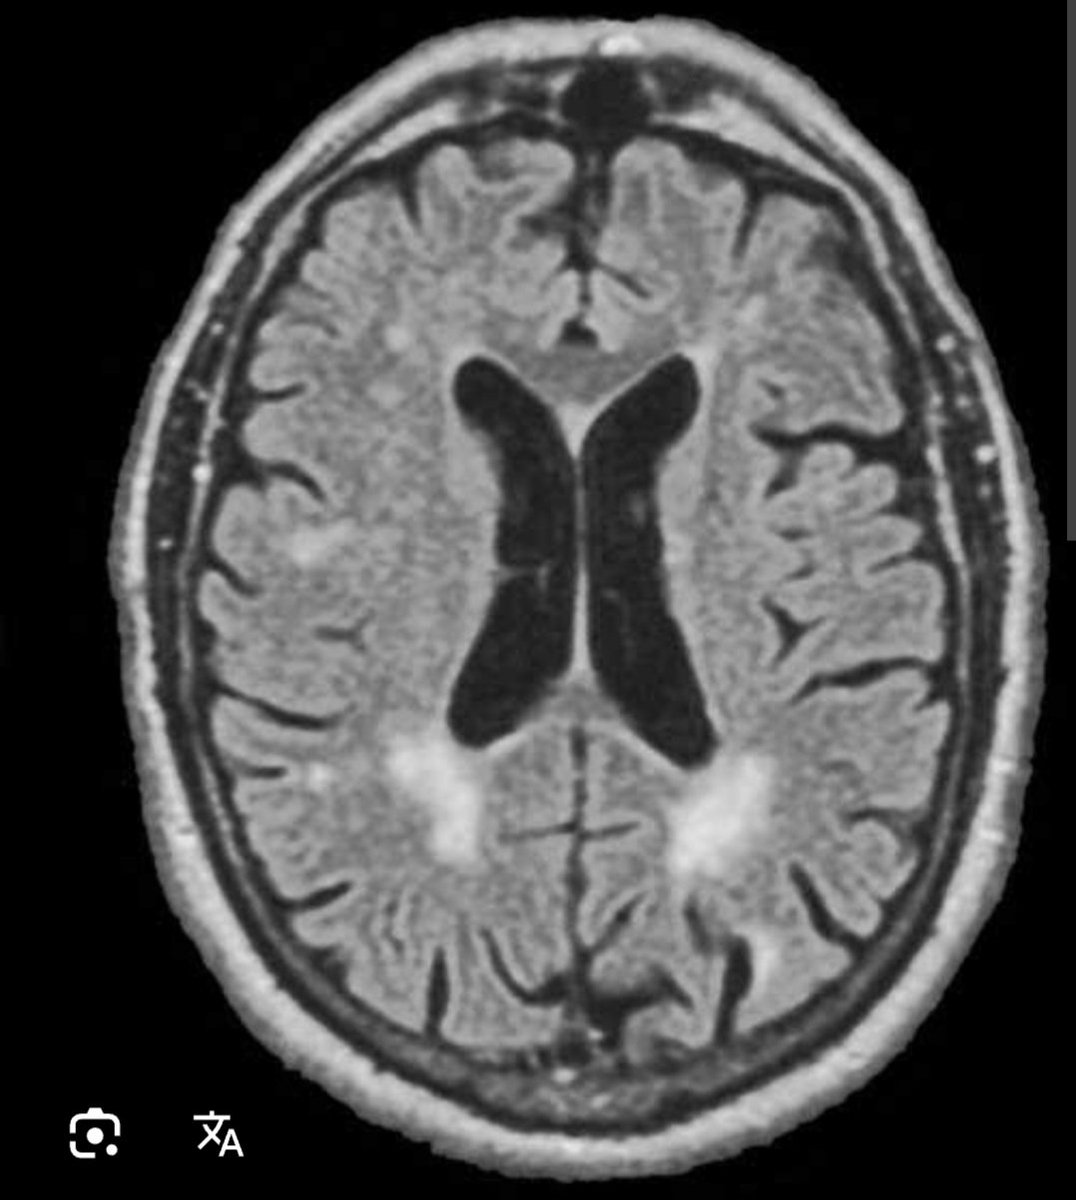

Fazekas 1 что это такое простыми словами 50 фото